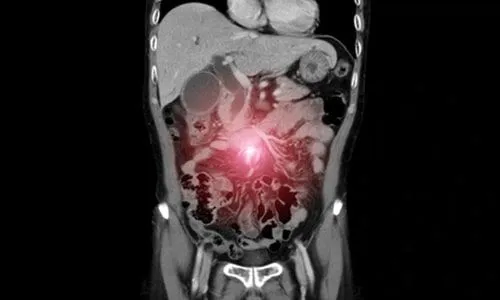

Periton karsinomatozisi, kanser hücrelerinin karın zarına (periton) yayılmasıyla ortaya çıkan ileri evre bir hastalık durumudur. Genellikle mide, kolon, pankreas veya over (yumurtalık) kanserlerinin ilerlemesi sonucunda gelişir ve klasik tedavi yöntemlerine göre daha kompleks bir yaklaşım gerektirir.

Periton karsinomatozisi, primer bir kanserin karın içine yayılması sonucu periton yüzeyinde çok sayıda tümör odağının oluşmasıdır.

Kanser hücreleri ana tümörden ayrılır ve karın boşluğuna yayılır. Yer çekimi ve periton sıvısının dolaşımıyla farklı bölgelere taşınarak burada tutunur ve çoğalmaya başlar.

- Bilgisayarlı tomografi (BT)

- Manyetik rezonans (MR)

- PET-CT